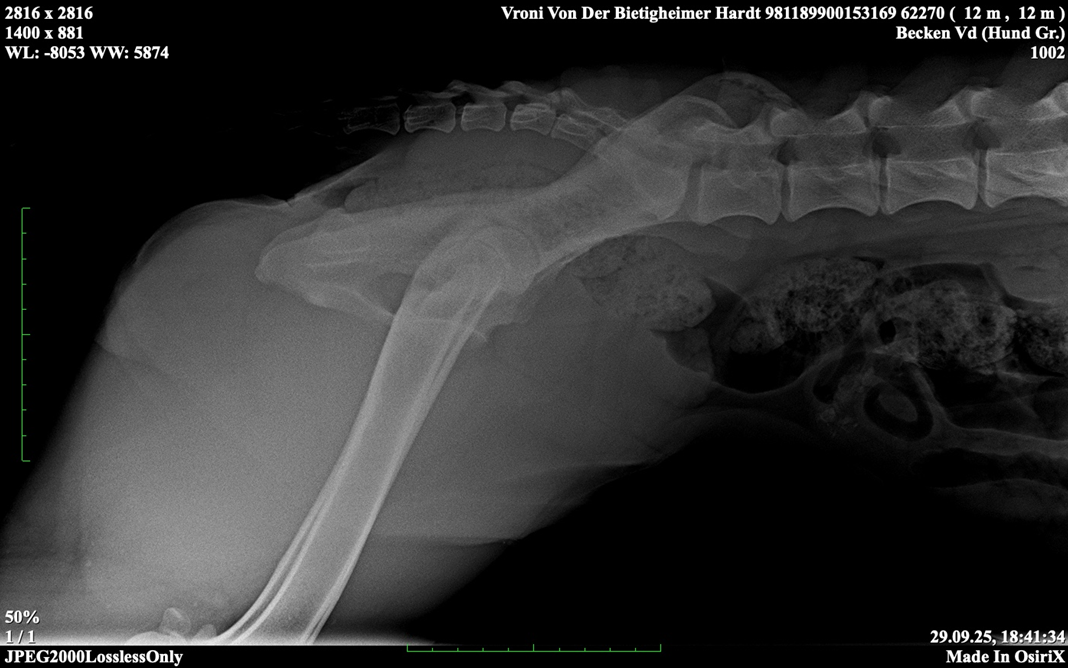

HD ZW: kW25/02 „69“ Größen-ZW: kW25/02 „101!